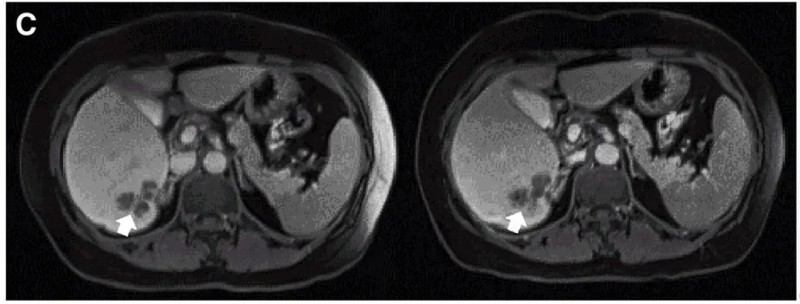

典型病例疗效尤为亮眼:P10患者接受DL4剂量治疗后,MRI证实肝内一处病灶缩小(详见下图)。

▼P10患者在CAR-T治疗前(左图)、治疗4周后(右图)的MRI对比

▲图源“Molecular Therapy”,版权归原作者所有,如无意中侵犯了知识产权,请联系我们删除